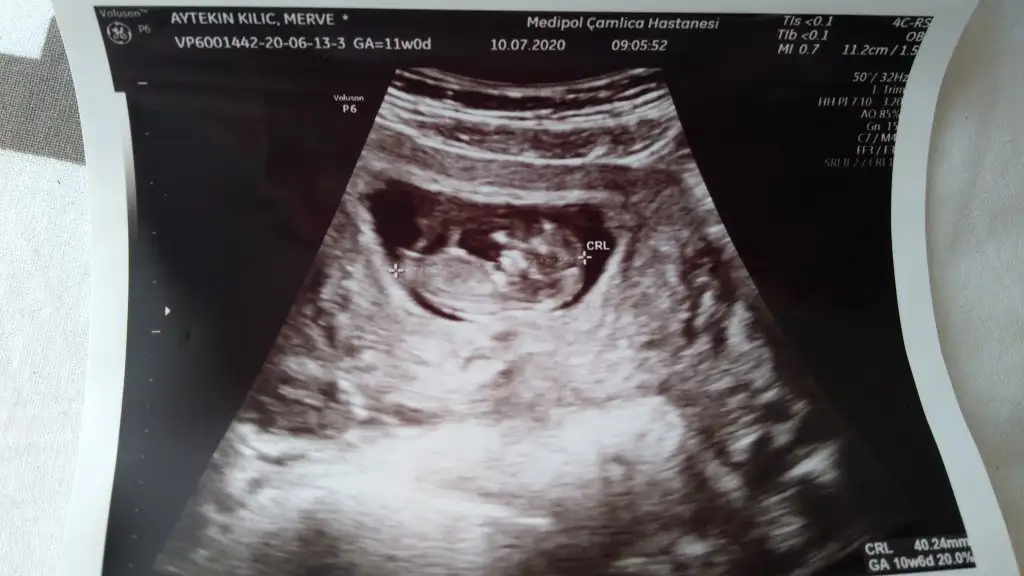

20200710_105611.webp 20200710_105530.webp

12+3 şuan. Bu seferki usg ler net çıkmadı maalesef ama yine bakabilir misiniz ? Biri usg çıktısı biri ekrandan foto çekimi.